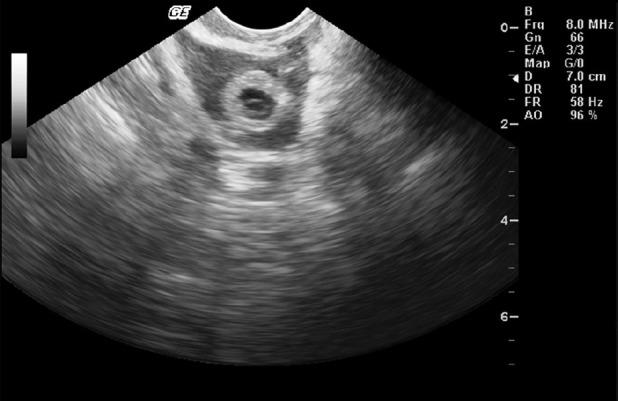

1例体外受精/卵胞浆内单精子注射术后未破裂的存活继发性卵巢妊娠经保守性腹腔镜手术治疗的罕见病例。

A rare case of unruptured viable secondary ovarian pregnancy after IVF/ICSI treated by conservative laparoscopic surgery.

Although the incidence of ectopic pregnancy is on the rise, ovarian pregnancy after in vitro fertilization and embryo transfer is a rare entity. Here, we report a case of unruptured ovarian pregnancy following in-vitro fertilization/intracytoplasmic sperm injection, which was treated by conservative laparoscopic surgery.

摘要

尽管异位妊娠的发生率呈上升趋势,但体外受精和胚胎移植后的卵巢妊娠是一种罕见情况。在此,我们报告一例体外受精/卵胞浆内单精子注射后未破裂的卵巢妊娠病例,该病例通过保守性腹腔镜手术进行了治疗。